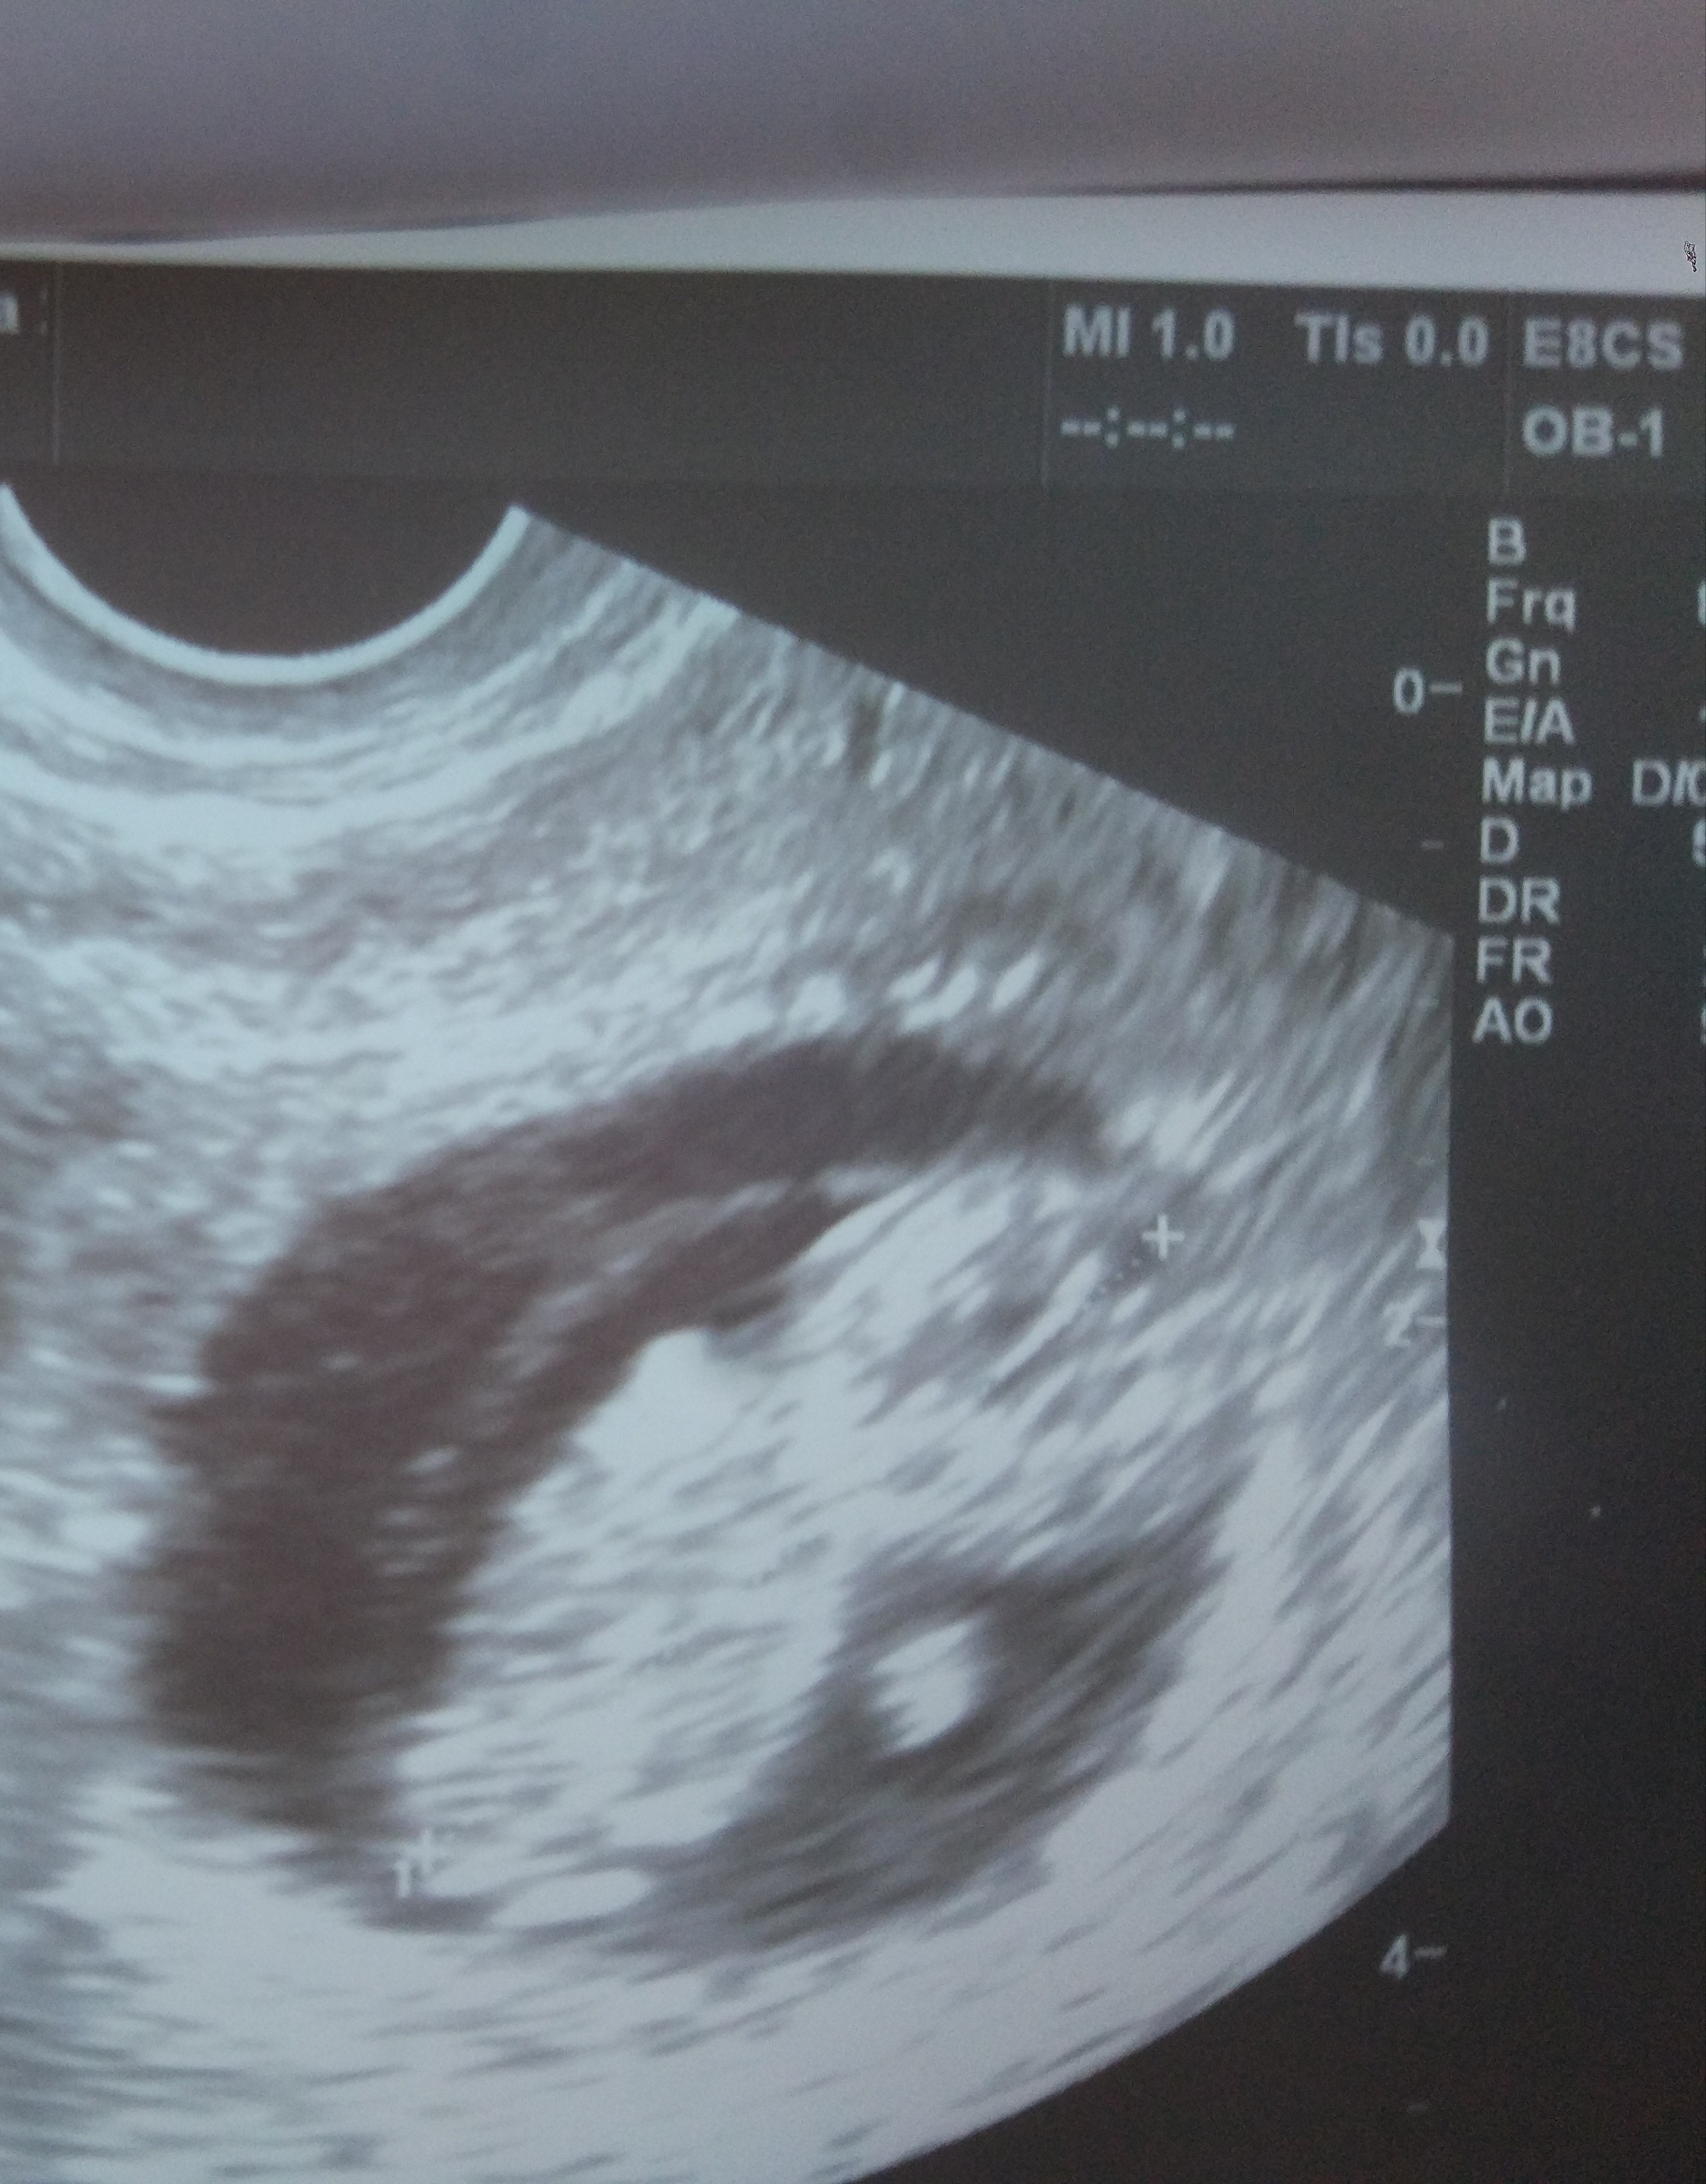

@sówka91 masz jakąś fotkę z dzisiejszej wizyty? Jesteśmy w podobnym czasie, ja mam dziś 9t2d. Masz już termin prenatalnych ?

Mam, mam, już wrzucam.. A na ekranie było jeszcze lepiej widać, już z rączkami i nóżkami :) Termin prenatalnych na 30.03, więc już niedługo.. Generalnie mam tyle pracy, że mega szybko zleci 😁

Aaaa jaki piękny człowieczek [emoji177][emoji177]

Mam, mam, już wrzucam.. A na ekranie było jeszcze lepiej widać, już z rączkami i nóżkami :) Termin prenatalnych na 30.03, więc już niedługo.. Generalnie mam tyle pracy, że mega szybko zleci [emoji16]